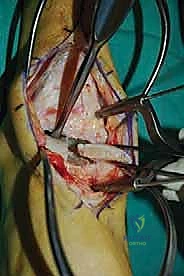

إمداد الكاحل بالدم: نقطة الضعف القاتلة

يُعد فهم إمداد عظم الكاحل بالدم أمراً بالغ الأهمية، وهو السر وراء فشل التئام العديد من إصابات هذا العظم. طبيعة الإمداد الدموي للتالوس هشة وضعيفة جداً، حيث يعتمد على شبكة دقيقة من الأوعية الدموية التي تدخل العظم من مناطق محددة. تساهم هذه الطبيعة الهشة في التحديات المرتبطة بآفات العظم الغضروفي (حيث يموت العظم لعدم وصول الدم) وتبرز أهمية التقنية الجراحية الدقيقة التي لا تدمر ما تبقى من أوعية.

أي تلف أو قطع في هذه الأوعية الدموية، سواء بسبب الإصابة الأصلية أو بسبب جراحة غير دقيقة، يمكن أن يؤثر سلباً وبشكل مدمر على قدرة العظم على الالتئام، مما يؤدي إلى حالة تُعرف بـ "النخر اللاوعائي" (Avascular Necrosis)، حيث يموت العظم تماماً. هنا تبرز عبقرية الأستاذ الدكتور محمد هطيف في استخدام الميكروسكوب الجراحي للحفاظ على هذه التروية الدموية الدقيقة.

الغوص العميق في جراحة الطعم الخيفي الهيكلي (Structural Allograft Reconstruction)

يهدف هذا الإجراء العبقري إلى استبدال الغضروف والعظم التالفين والميتين بنسيج سليم تماماً مأخوذ من متبرع متوفى (طعم خيفي - Allograft). هذا الطعم يتم تعقيمه وحفظه في بنوك الأنسجة العالمية وفقاً لأعلى المعايير الطبية الصارمة لضمان خلوه من أي أمراض معدية والحفاظ على حيوية الخلايا الغضروفية.